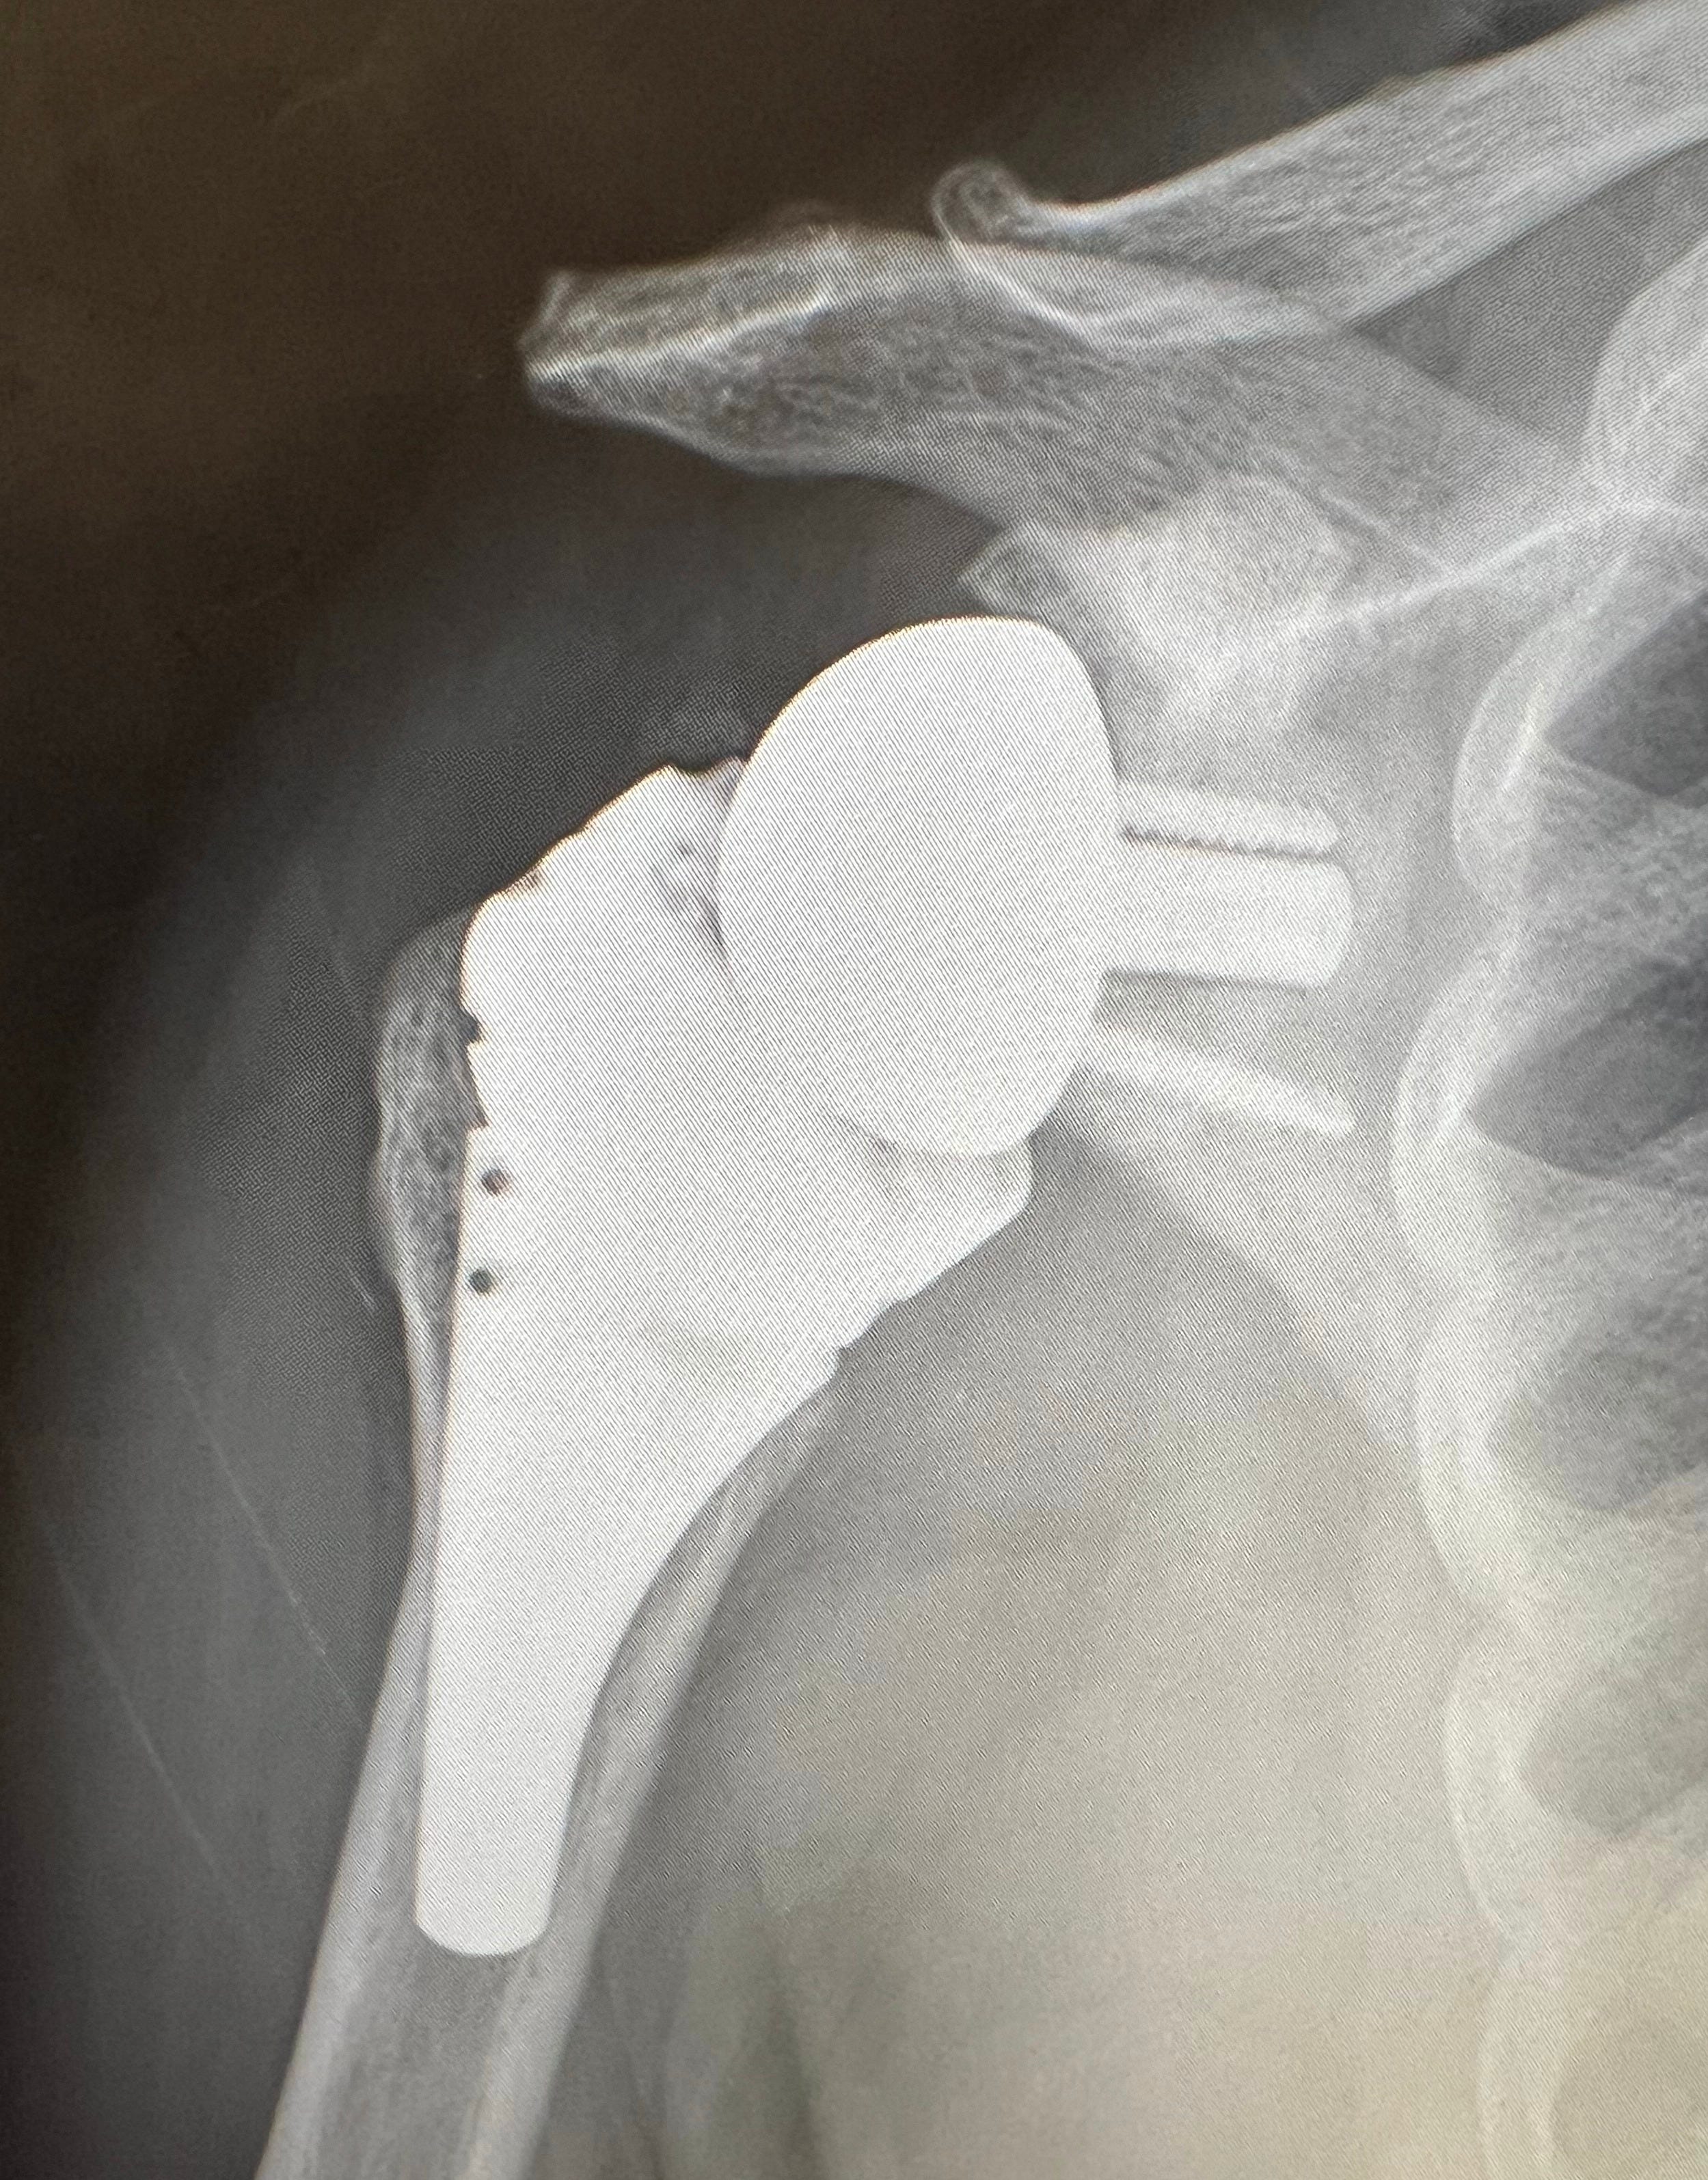

Total shoulder arthroplasty (replacement) has seen an increasing prevalence with technological advancements over the past thirty years. One of the most common questions I encounter in my practice is how new is the shoulder replacement procedure? The consensus from medical and laypeople is that shoulder replacement is a new procedure without long-term data to support its utilization. The shoulder replacement has spanned over 130 years, with the first shoulder replacement performed by French Surgeon Jules Emile Péan in 1893. The patient was a 37-year-old gentleman with advanced tuberculosis. The prosthesis significantly improved his quality of life for 2 years prior to infection, necessitating its removal. The prosthesis is on display at the Smithsonian Institution. Dr. Charles Neer, an American Orthopaedic Surgeon in the 1950’s, developed the Neer I prosthesis, a partial replacement that became standard until his Neer II design in the 1970’s, which addressed the glenoid and became a Total Shoulder. In 1987, my mentor, Dr. Wayne ‘Buz’ Burkhead, developed the Select Modular Shoulder prosthesis, becoming the first modular total shoulder system. Around the same time, in the late 1980’s, Dr. Paul Grammont began developing the reverse Total Shoulder for the treatment of rotator cuff-deficient shoulder arthritis. Since completing my Shoulder and Elbow Fellowship in 2006 with Dr. Burkhead, I have witnessed the technological explosion in total shoulder prosthesis. This has resulted in increased indications and patient outcomes. Harkin et al.’s study from 2025 reveals that surgeons who perform more than 20 total shoulder replacements per year have significantly lower complication rates. Being a Subspecialist in Shoulder and Elbow, I specialize in managing complex shoulder and elbow disorders.